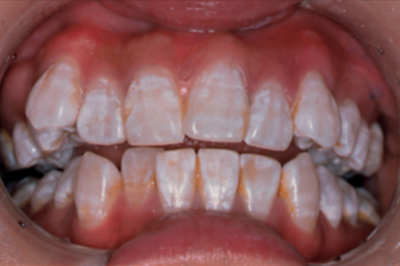

第109回 C問題 52問目 - 109C052

歯の変色

27歳の女性。歯の変色を主訴として来院した。初診時の口腔内写真を別に示す。最も疑われる原因はどれか。1つ選べ。

a. 加齢

b. 喫煙

c. 先天性梅毒

d. 習慣性嘔吐

e. フッ化物の長期過剰摂取